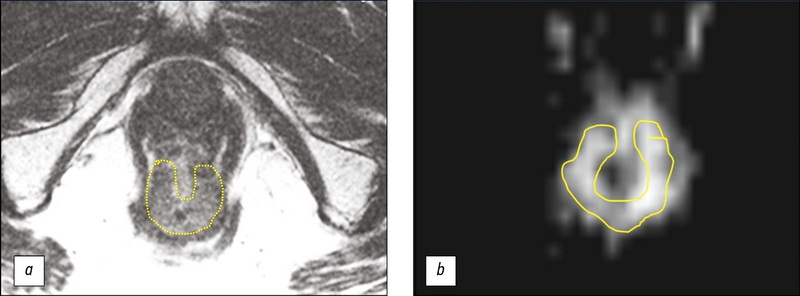

MRI evaluation of the neoadjuvant chemoradiation therapy result in a patient with rectal cancer, supplemented with T2-WI texture analysis of the tumor: a clinical case

The article presents a clinical case of using the active follow-up strategy (the so-called watch & wait) in a 73-year-old patient with cancer of the lower rectum with a good response to neoadjuvant chemoradiation therapy (NCRT). After 3 years of regular follow-up, including digital rectal examination, rectoscopy and MRI, indicating the absence of tumor progression, PET/ CT with 18F-FDG was obtained, which revealed a region of hypermetabolic activity in the lower rectum (SUVmax 27.1), in connection with which it was decided to carry out surgical treatment. When discussing the issue of the volume of the operation, MRI data were taken into account, supplemented by the results of T2-weighted texture analysis, which confirmed the absence of progression. The patient underwent organ-preserving treatment in the amount of transanal tumor resection. Pathomorphological examination after surgery established the inflammatory changes in the intestinal wall and absence of tumor. This case demonstrates the effectiveness of the standard examination volume when using the watch & wait strategy and the possibility of using T2-WI texture analysis to increase the reliability of MRI assessment of tumor response to chemotherapy.